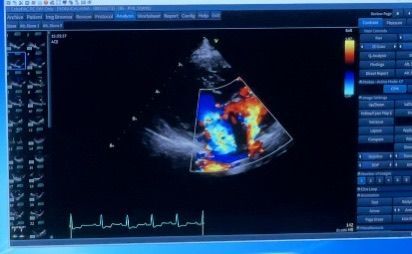

直近(2021年6月29日)愛媛の病院の心臓検査の結果

2021年6月11日愛媛から大阪にある、近畿動物医療研修センター付属動物病院さんに行き、まずは精密検査を行いました。

心電図・血圧・✕線・心臓エコー・全血球検査・血液生化学検査を行った結果、色が付いている左心房への逆流が5割で重度なのに、ひなは6、7割になっており、かなり重度と言われました。